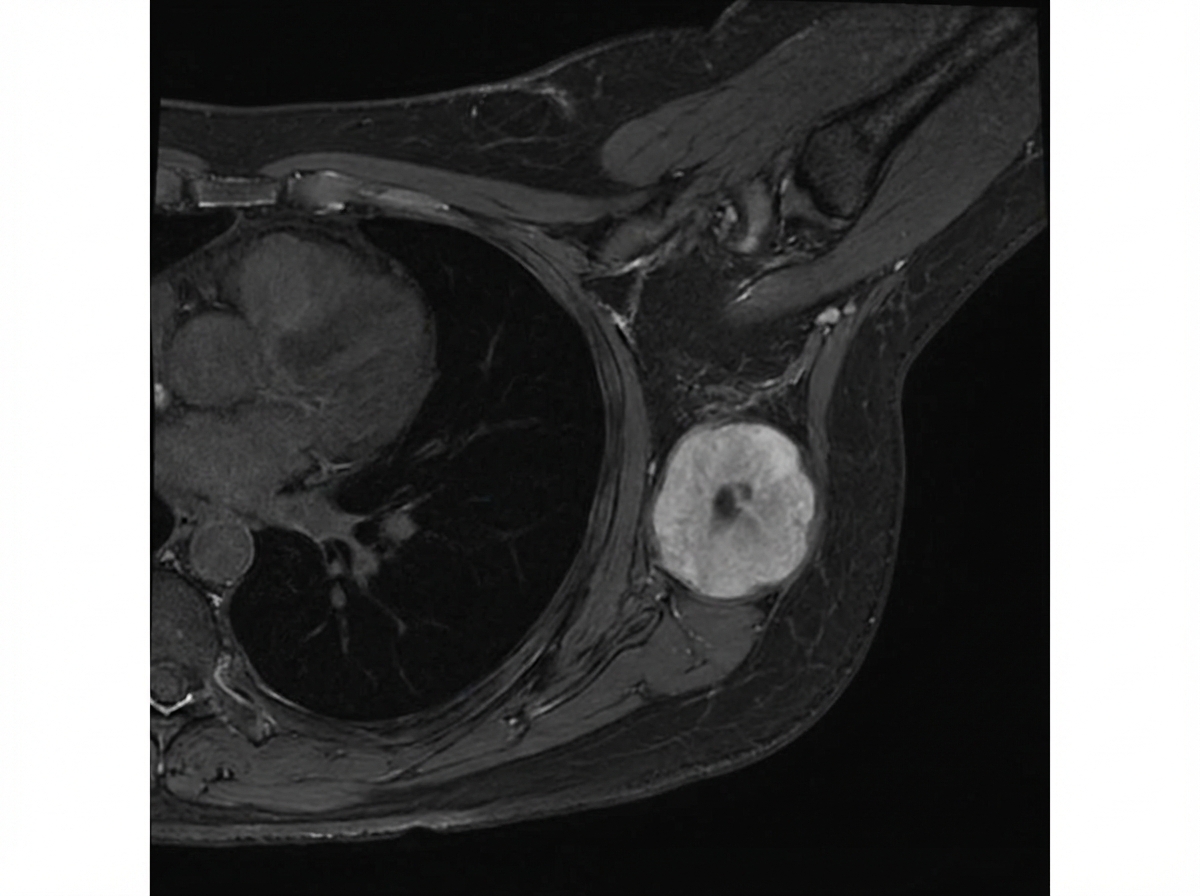

In the MRI breast shown below, 4 cm mass is present with no nodal metastasis. Which is the stage of breast cancer?

Explanation: ***Stage II*** - A tumor of **4 cm** with no nodal metastasis is classified as pT2, N0, M0. This falls under **Stage IIA** breast cancer according to the TNM staging system. - Stage II breast cancer typically includes tumors that are larger than 2 cm but not larger than 5 cm (T2N0), or smaller tumors with lymph node involvement. - The **4 cm size with N0 status** specifically defines Stage IIA. *Stage 0* - Stage 0 represents **ductal carcinoma in situ (DCIS)** or **lobular carcinoma in situ (LCIS)**, which are non-invasive breast cancers. - This case describes a **4 cm mass**, indicating an invasive tumor, not in-situ disease, ruling out Stage 0. *Stage I* - Stage I breast cancer includes tumors that are **2 cm or smaller** (T1) and have no lymph node involvement (N0). - Since the mass is **4 cm**, it exceeds the size criteria for Stage I. *Stage III* - Stage III breast cancer involves **larger tumors** (greater than 5 cm) or any tumor size with extensive lymph node involvement, or tumors invading the chest wall/skin. - While this mass is 4 cm, there is **no nodal metastasis**, which rules out Stage III. *Stage IV* - Stage IV breast cancer indicates the presence of **distant metastases** (M1), meaning the cancer has spread to other parts of the body. - The information provided clearly states **no nodal metastasis**, and no information about distant spread, therefore Stage IV is incorrect.